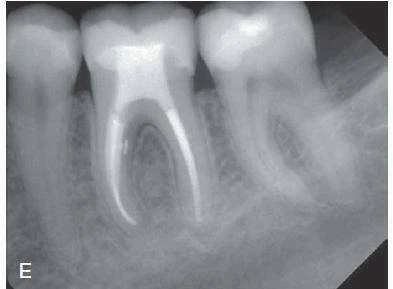

Rất nhiều các yếu tố trước và sau khi điều trị được cho là có liên quan tới kết quả điều trị nội nha. Những yếu tố này bao gồm tuổi và giới tính của bệnh nhân, vị trí của răng trên cùng hàm, độ rộng của ống tuỷ, các vật liệu băng ống tuỷ giữa các lần hẹn. Ví dụ như canxi hidroxit [Ca(OH)2]. Sự có mặt của các tổn thương xương cận chóp (ví dụ bệnh viêm nha chu chóp răng) được coi là một yếu tố tiên lượng làm giảm kết quả khả quan của điều trị tuỷ răng. Tuy nhiên, kích thước của tổn thương không phải là chỉ định để quyết định phẫu thuật nội nha. Hình 9-4 cho thấy hai trường hợp có tổn thương xương lớn được điều trị bằng phương pháp nội nha thông thường (từ trên xuống hay hướng thuận). Đối với những lần hẹn tiếp theo, răng đã không có triệu chứng, và kích thước tổn thương giảm hẳn cho cả hai ca.

Một số câu hỏi được đặt ra liên quan tới tổn thương như trường hợp trong hình 9-4 chính là về nang. Nhiều nghiên cứu đã chứng minh rằng, kích thước của tổn thương cho thấy ít có sự liên quan với tỉ lệ có nang chân răng. Chỉ có xét nghiệm mô học mới có thể chứng minh vùng thấu quang xuất hiện trên phim X-quang có phải là nang hay không. Các nang thật sự sẽ được lấy bỏ bằng nạo phẫu thuật, trong khi đó, phần lớn các tổn thương không phải nang ở chóp răng sẽ liền thương sau điều trị nội nha thông thường mà không cần phẫu thuật. Do đó cách tiếp cận nội nha theo hướng thuận được sử dụng rộng rãi cho các trường hợp lâm sàng không có triệu chứng và cần hẹn tái khám với các khoảng thời gian phù hợp.

Hình 9-4. Điều trị tuỷ trong trường hợp phá huỷ đáng kể cận chóp. A – Hình ảnh phim chụp trước điều trị của răng#8 và #9 cho thấy tổn thương lan rộng, răng không đáp ứng với thử lạnh. B – Hình ảnh phim chụp tái khám sau 2 năm cho thấy có tái tạo xương. Các ống tuỷ được tạo hình với dụng cụ cầm tay và các file máy và trám bít lèn bên bằng gutta-percha với chất AH Plus. C – Hình ảnh phim chụp trước điều trị của răng #4, cho thấy ống tuỷ trám bít, tổn thương cận chóp rộng và quan sát thấy trám bít chưa hoàn thiện. D – Hình ảnh phim chụp tái khám sau 2 năm cho thấy sự liền thương xương mà không điều trị phẫu thuật(A-B Courtsy Dr.M.Zehnder; C-D Courtesy Dr.E.Paque)